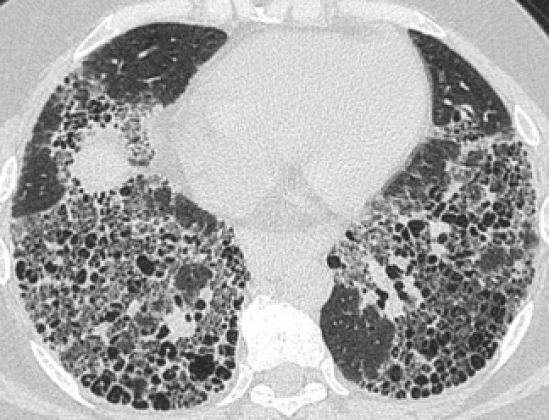

La Fibrosis Pulmonar Idiopática es una enfermedad crónica, progresiva y letal, con una elevada mortalidad de 50% a 3 años posterior del diagnóstico en la historia natural, gravemente incapacitante y, a la larga, letal que en México tiene una incidencia anual estimada de 6 a 8 casos por cada 100,000 habitantes y prevalencia de 14 por cada 100,000 habitantes, en el mismo periodo.

Agregó que la FPI se limita al pulmón, al intersticio pulmonar que rodea a los alvéolos pulmonares, donde se produce el intercambio de oxígeno por dióxido de carbono y viceversa. Este tejido desarrolla cicatrices y se vuelve rígido, sin elasticidad, lo que dificulta la respiración, produciendo un sonido como el que causan las pisadas sobre la nieve, o un crujido como el que emite la separación de una tira de velcro.

Al no ser una enfermedad “frecuente” pero si devastadora que en ocasiones no se hace mención de ella de manera habitual. Se trata de un padecimiento que afecta directamente a la calidad de vida de los pacientes, limitando sus actividades diarias, agregó la Dra. Buendía, por ello, añadió de la importancia de conocer y trabajar en beneficio de la población afectada por esta enfermedad, ya que uno de los principales problemas de la FPI es la dificultad de un diagnóstico certero, pues suele confundirse con otros padecimientos respiratorios.